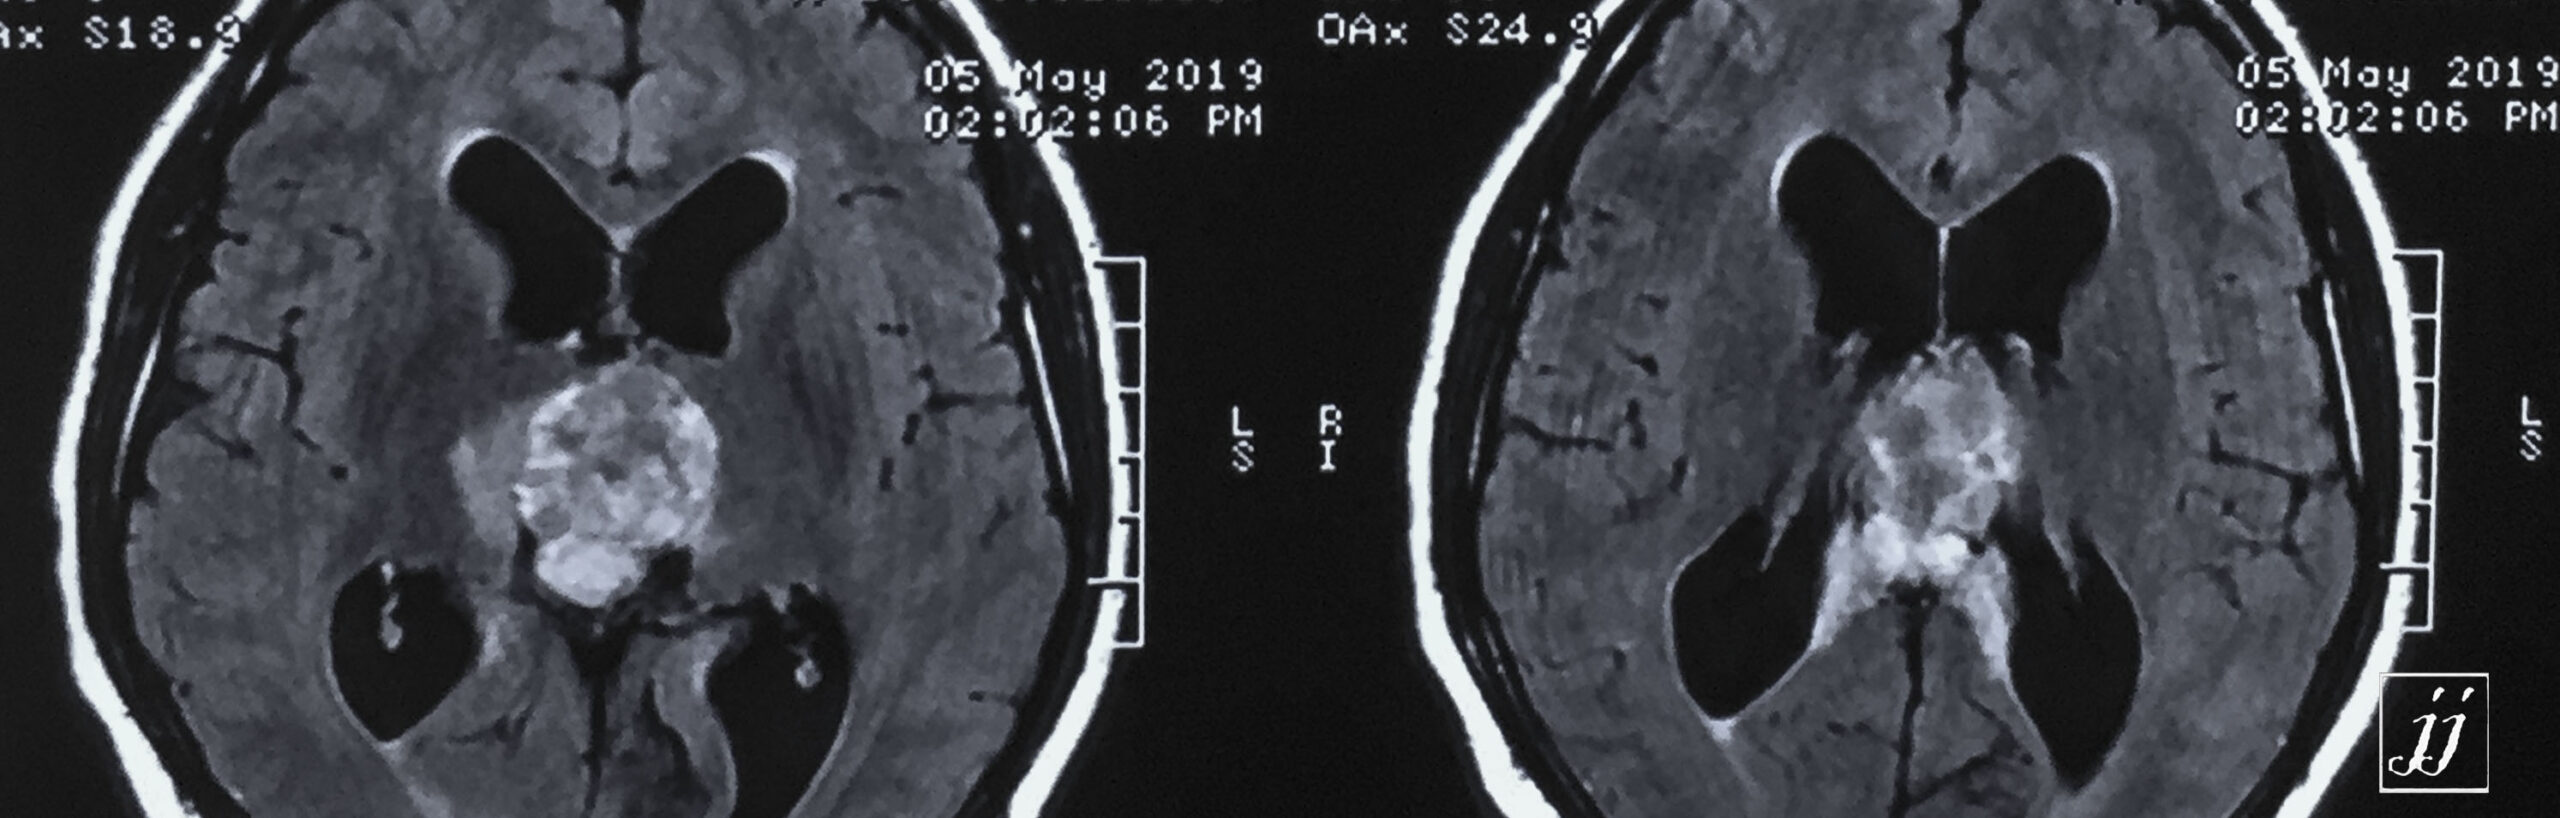

Brain- hugged size tectal and quadrigeminal meningioma (2)